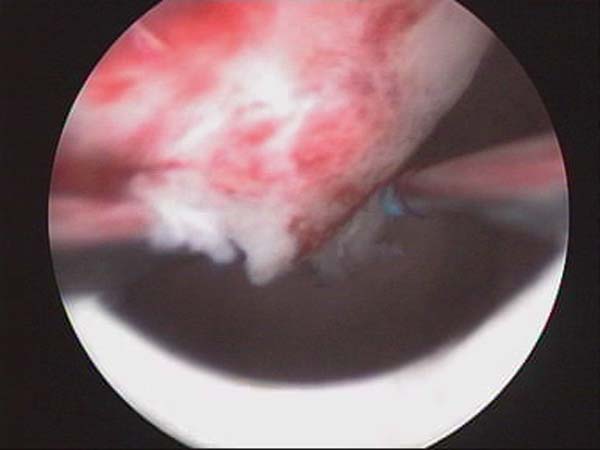

- Photos de l’hystéroscopie

Photos de l’hystéroscopie | Dr N Layyous